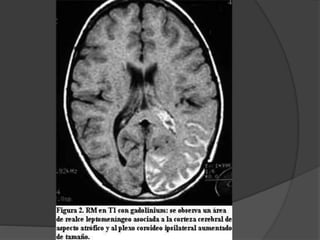

Enfermedad de Sturge-Weber Angiomatosis encefalotrigeminal  Etiopatogenia desconocida  Mas frecuente dentro de los sindromes neurocutaneos con predominio de anomalias vasculares.

La lesion fundamentales una malformacion vascular de tipo telangiectasico-venoso que afecta:  la coroides (angioma coroideo)  la cara (angioma facial)  el cerebro (angioma leptomeningeo) Puede ser del mismo lado, bilateral o presentarse inclompleto. Mancha en vino de oporto

Otras afecciones  Buftalmos Glaucoma  Epilepsia  Calcificaciones cerebrales  Retraso mental  Hemianopsia  Hemiparesia